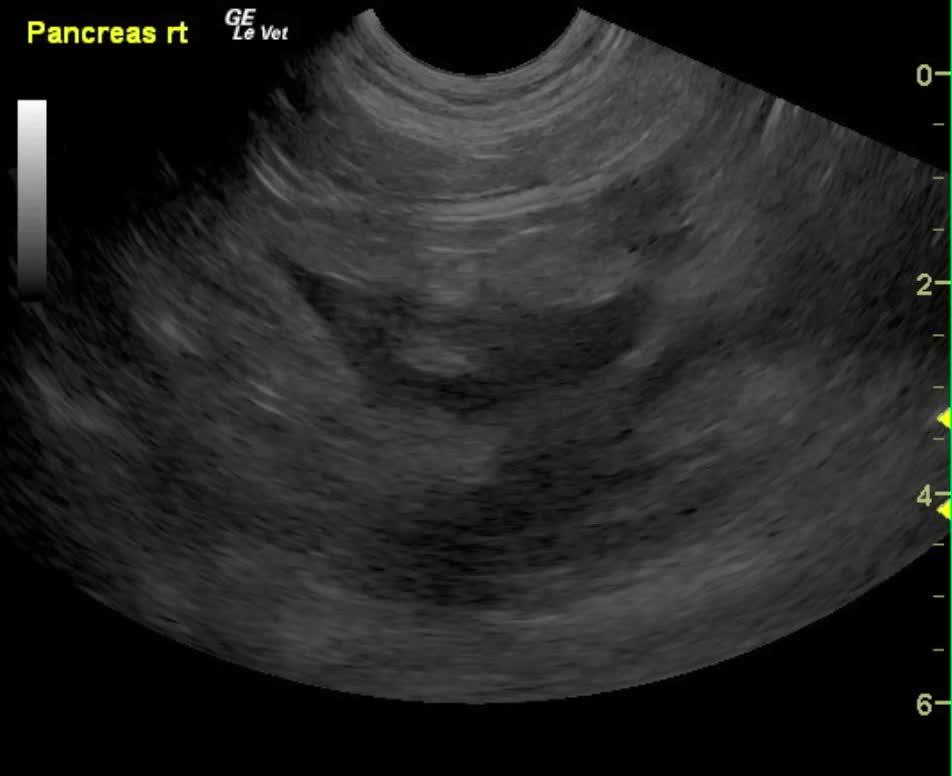

A 9-year-old MN DSH was presented for evaluation of lethargy, inappetence, and diarrhea. On physical examination, moderate dental tartar, poor body condition (BCS 2/5) and a dull unkempt hair coat was evident. On urinalysis moderate leukosuria, mild hematuria, and normal SG with moderate leukocytes, 2+ protein, 6.5 pH, urine specific gravity 1.035 with a small amount of blood. Abnormalities on CBC and serum biochemistry were neutrophilia with toxic changes, hyperglycemia, hyperglobulinemia, elevated fPL, and low folate and low B12. Negative FeLV, negative FIV, and negative heartworm assay. On survey radiographs mild hepatomegaly was evident.